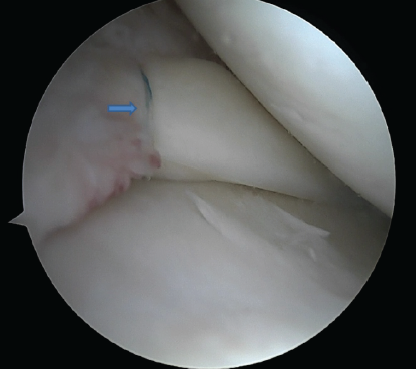

The torn meniscus edges were freshened using a rasp and shaver to promote healing and remove perisynovial tissue. A trocar was used to push the bucket-handled part of the meniscus to its original place close to the capsule. The outside-in reduction stitch was deployed first to reduce and hold the meniscus in place for both the medial and lateral menisci. Identifying the anterior edge of the medial collateral ligament by palpation is very imperative and serves as an important landmark because the first outside-in should be placed in the mid-body of the meniscus. A box stitch configuration is used to peripheralize the meniscus and prevent the meniscus from entering the center of the joint and thus aiding in further vision for all inside stitches (Fig. 3).

Figure 3: Reduced medial meniscus with a single outside-in stitch.